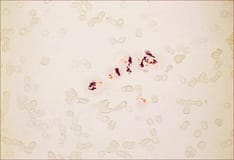

Escherichia coli on Gram stain. Gram-negative bacilli.